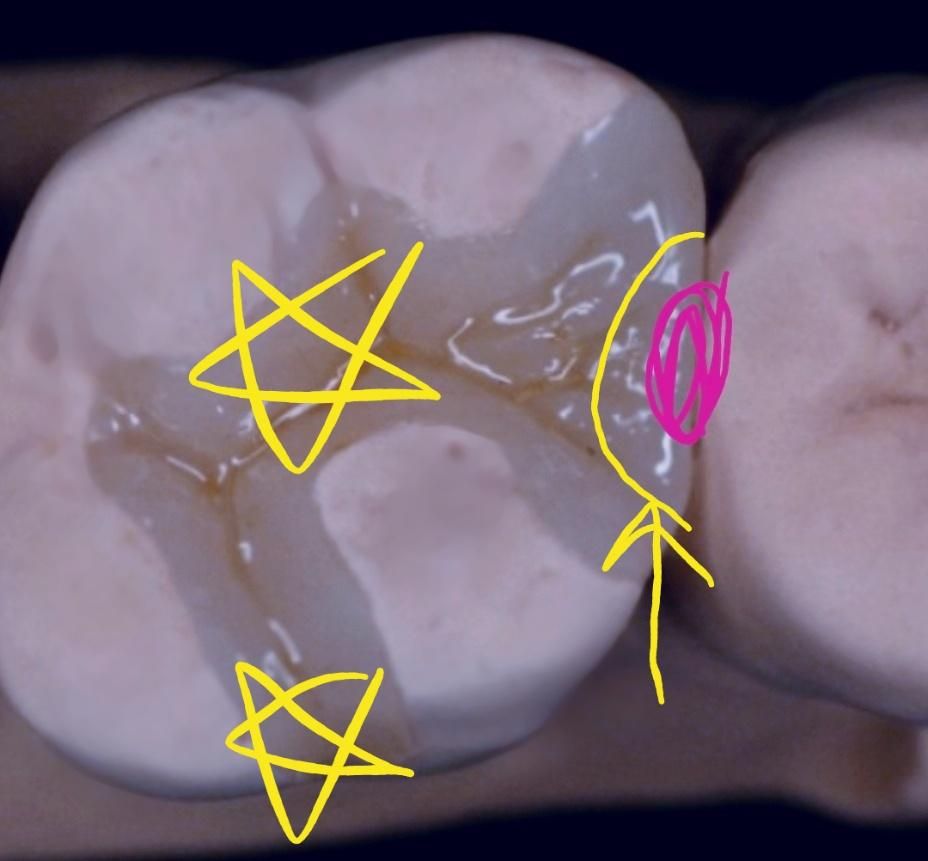

인레이 과잉인지 확인해주세요... .

빨간색 표시있는 인접면에 초기 충치 있었습니다 . 그런데 인레이를 사진과같이 와동을 만들어씹는면이 삭제가 되었습니다

레진으로 노란색(화살표) 만큼만 파서 치료를 하면 안되는건가요?

인접면에 충치가 잇는경우 저정도만 삭제를 하게되면 유지력이 나오지 않습니다. 그래서 조금더 확장해서 인레이를 형태를 만들어 줍니다.

인레이 치료를 하게 되면 적절한 접착과 형태를 유지하기 위해서는 이상적인 와동형태에 가깝게 진행해야 합니다.

인레이는 교과서적으로 모양이 정해져 있습니다. 노란색 화살표 만큼만 삭제하고 레진으로 치료도 가능하지만

현실적으로 우리나라에서 치료하는 치과는 많지는 않습니다^^;;

인레이의 유지력 및 지지력을 위해서 어쩔 수 없이 만드는 인레이 외형입니다. 옆면만 팔 경우 잘 빠질 수 있습니다.

레진치료의 경우에는 거의 충치만 제거하고 해당 부위를 수복하지만 인레이의 경우에는 보철물의 삽입철거로( 보철물을 붙였다 떼어냈다하는 경로)가 필요해서 아무래도 치아삭제량이 많아집니다.

또한 충치가 생겼다는 것은 아무래도 해당치아가 관리가 잘되는 편은 아니였다고 볼 수 있고 인레이 수복 전 치아의 상태를 보지는 못했지만 육안으로 봤을때 괜찮아 보인다고 하더라도 치아의 씹는면에는 열구라고 하는 계곡같이 움푹 패이고 깊은 골짜기가 있는데 이러한 곳은 충치가 생기기도 쉽고 이미 숨겨진 충치가 있었을 수도 있어서 인레이 치료를 하시면서 해당 부위들도 추후에 충치발생 가능성이 높아져서 일부러 인레이 수복 범위에 포함시켰을 수도 있습니다.